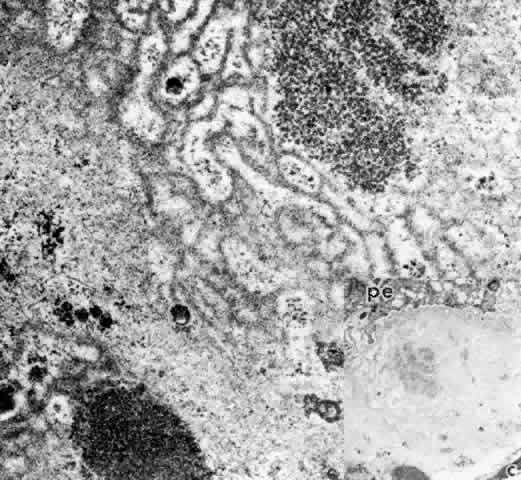

Fig. 26. Inset. Greatly thickened basal lamina under pigmented epithelial cell in (pe) pars

plicata of 80-year-old patient. c, capillary. Higher magnification

of area in inset shows mixed multilaminar and solid basement

membrane with fine filaments, vesicles, and granular clumps, after fixation

with Alcian blue to preserve glycosaminoglycans. (X 41,600; inset, X 10,330) Fig. 26. Inset. Greatly thickened basal lamina under pigmented epithelial cell in (pe) pars

plicata of 80-year-old patient. c, capillary. Higher magnification

of area in inset shows mixed multilaminar and solid basement

membrane with fine filaments, vesicles, and granular clumps, after fixation

with Alcian blue to preserve glycosaminoglycans. (X 41,600; inset, X 10,330)

|